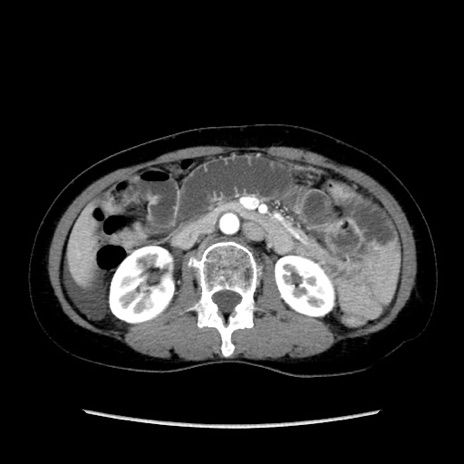

症例32(横断像)

【症例】40歳代 女性

【主訴】上腹部痛、嘔気・嘔吐

【現病歴】約9時間前頃から急に上腹部痛、嘔気、嘔吐が出現。改善しないため救急要請。

【既往歴】子宮頚癌(広汎子宮全摘術、放射線療法)、腸閉塞

【身体所見】腹部:平坦、軟、腸雑音亢進、上腹部を中心に腹部全体に圧痛あり。

【データ】WBC 8400、CRP 0.03